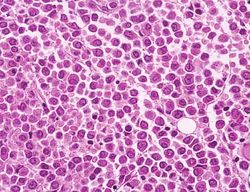

Associazione donatori midollo osseo di Piacenza - Progetto di ricerca immunogenetica

Associazione donatori midollo osseo di Piacenza - Progetto di ricerca immunogeneticaLo stanziamento è relativo al finanziamento di un progetto di ricerca immunogenetica dell’Admo presso il centro trasfusionale. In particolare, il contributo della Fondazione di Piacenza e Vigevano alla ricerca si concretizza con il pagamento di una borsa di studio riservato ad una biologa, che ha frequentato il laboratorio acquisendo esperienza nelle tecniche di tipizzazione al citofluorimetro e nel congelamento delle cellule staminali.

Il laboratorio di Immunogenetica HLA, parte integrante del servizio di Immunoematologia e Medicina trasfusionale dell’ospedale di Piacenza, dal 2009 è accreditato - unico in regione insieme al centro di Immunogenetica di Bologna - dall’European Federation for Immunogenetics (Efi). Svolge attività per definire le caratteristiche genetiche richieste per i donatori di midollo osseo che vogliono iscriversi al registro IBMDR (Italian Bone Marrow Donors Registry) di cui il laboratorio fa parte come Centro Donatori e Centro Prelievi di midollo osseo.

Inoltre, studia le caratteristiche genetiche dei pazienti oncoematologici da avviare al trapianto di midollo allogenico (da donatore a ricevente) e la suscettibilità genetica dei pazienti con sospette patologie autoimmuni.

Altre ricerche riguardano: l’utilizzo di farmaci in base all’assetto genetico dei pazienti in particolari regimi terapeutici (farmocogenetica e terapie personalizzate); la genetica dei gruppi sanguigni; le mutazioni genetiche per la diagnosi dell’emocromatosi ereditaria.

Il laboratorio conta la presenza di due biologi specializzati in ruolo, e l’aiuto (condiviso con il laboratorio di citofluorimetria e cellule staminali) di una biologa specializzanda in Patologia clinica. La borsa di studio che sostiene l’attività della specializzanda è stata istituita ad aprile 2011 dall’Admo-Associazione donatori di midollo osseo, grazie a fondi in maggior entità erogati dalla Fondazione di Piacenza e Vigevano.

Nel 2011 la Fondazione di Piacenza e Vigevano ha contribuito al progetto con un sostegno di 10.000,00 €.